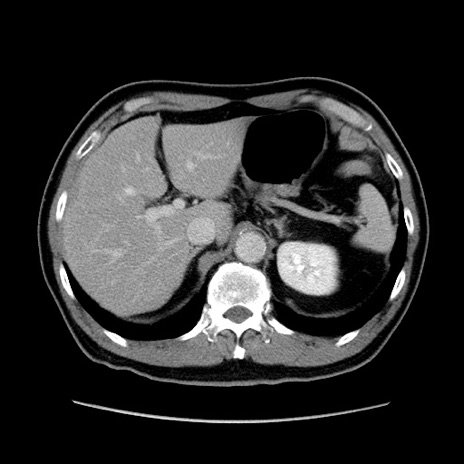

症例34(横断像)

【症例】60歳代 男性

【主訴】右鼠径部膨隆

【現病歴】1年程前より右鼠径部膨隆あり。自己にて還納可能だったため放置していた。3時間前より右鼠径部の脱出を認め、還納困難となり受診。

【既往歴】高血圧

【身体所見】右鼠径部に小児頭大の膨隆あり。弾性硬であり、用手還納は困難。左鼠径部にも膨隆を認める。脱出はなし。

【データ】WBC 15500、CRP 測定なし